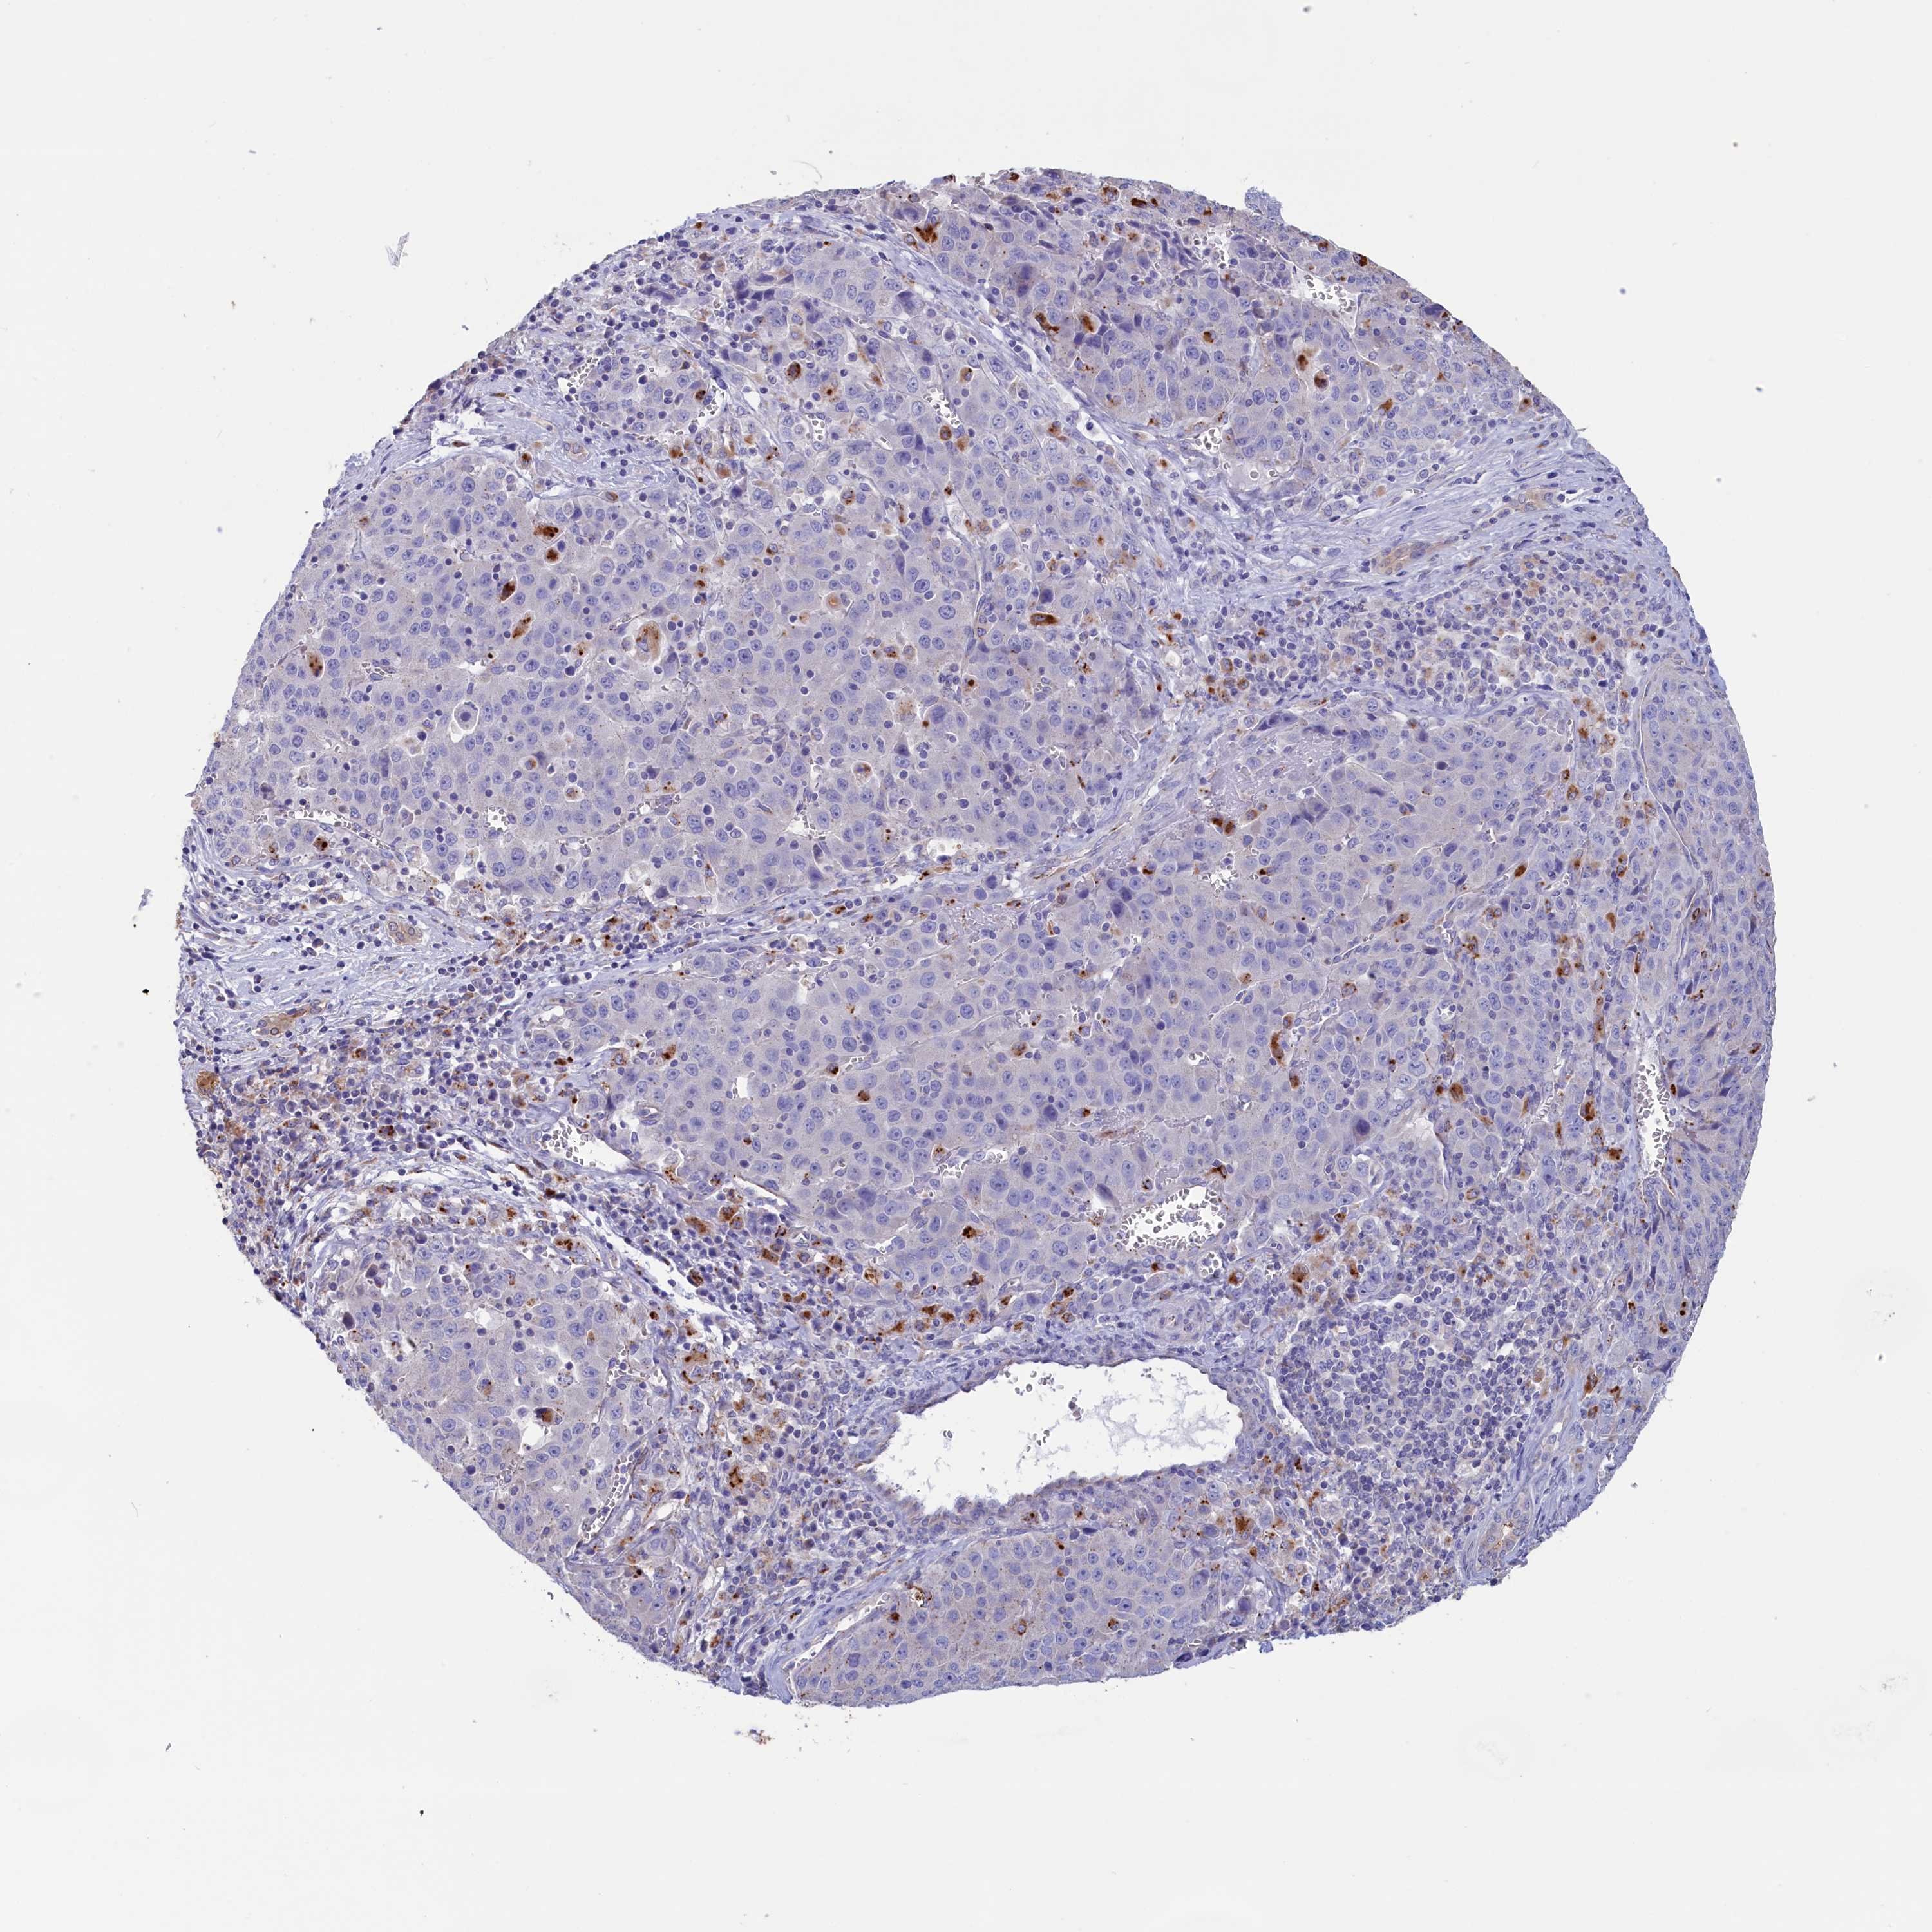

LIVER CANCER - Protein expressioni

A mouse-over function shows sample information and annotation data. Click on an image to view it in a full screen mode. Samples can be filtered based on level of antibody staining by selecting one or several of the following categories: high, medium, low and not detected. The assay and annotation is described here.

Note that samples used for immunohistochemistry by the Human Protein Atlas do not correspond to samples in the TCGA dataset.

Antibody stainingi

Antibody staining in the annotated cell types in the current human tissue is reported as not detected, low, medium, or high, based on conventional immunohistochemistry profiling in selected tissues. This score is based on the combination of the staining intensity and fraction of stained cells.

Each image is clickable and will lead to virtual microscopy that enables deeper exploration of all samples and also displays staining intensity scores, fraction scores and subcellular localization as well as patient and tissue information for each sample.

Antibody HPA042622

Staining

High

Medium

Low

Not detected

Intensity

Strong

Moderate

Weak

Negative

Quantity

>75%

75%-25%

<25%

None

Location

Nuclear

Cytoplasmic/membranous

Cytoplasmic/membranous,nuclear

Cholangiocarcinoma

Carcinoma, Hepatocellular, NOS